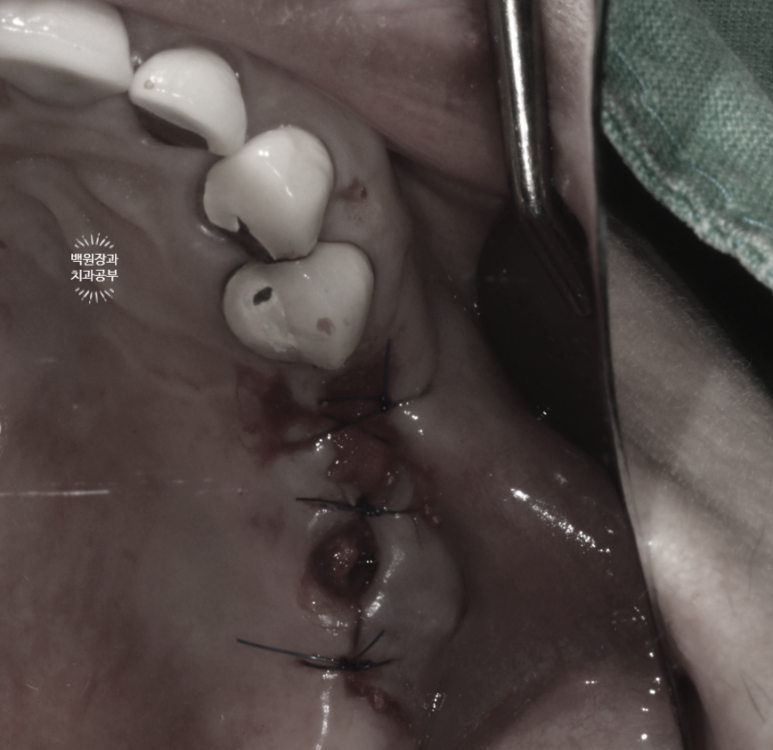

깨끗하게 제거하고, 염증 조직을 모두 제거해드린 뒤 깔끔하게 꿰매 드렸습니다.

오른쪽 위 임플란트 2개를 제거하고, 뼈이식을 하였습니다.

임플란트를 제거하고 다시 임플란트를 새로 식립할 계획이었기 때문에, 뼈이식을 함께 해드리기로 계획하였어요.

뼈이식을 하였으면, 재료가 빠져나오지 않게 입구를 닫아주어야겠죠?

콜라겐으로 구성되어 있어 약 1-2주면 흡수되면서, 임플란트를 제거했던 입구가 잇몸으로 차오르게 도와줍니다.

임플란트 주위염이 너~무 심하셔서, 제거하고 났더니 출혈이 상당히 심하더라구요 ㅠㅠ

그래서 염증조직을 빠르게 제거 후 Bio-Oss collagen 250mg 을 나누어 적용하였습니다.

그리고 임플란트를 뽑아내었기 때문에 동그랗게 비어있는 잇몸 위치는

Collgen graft 2 10C를 사용하여 막아주기!

깔끔하게 수술이 끝났지요 :)